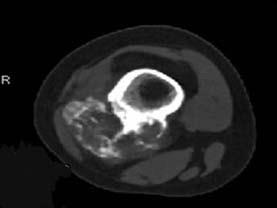

问题 女,20岁,右大腿远端疼痛2年,伴有肿块,请结合所提供图像,选择最佳答案 ( )

选项 A、纤维肉瘤 B、骨巨细胞瘤 C、软骨肉瘤 D、骨肉瘤 E、软骨黏液纤维瘤

答案 C